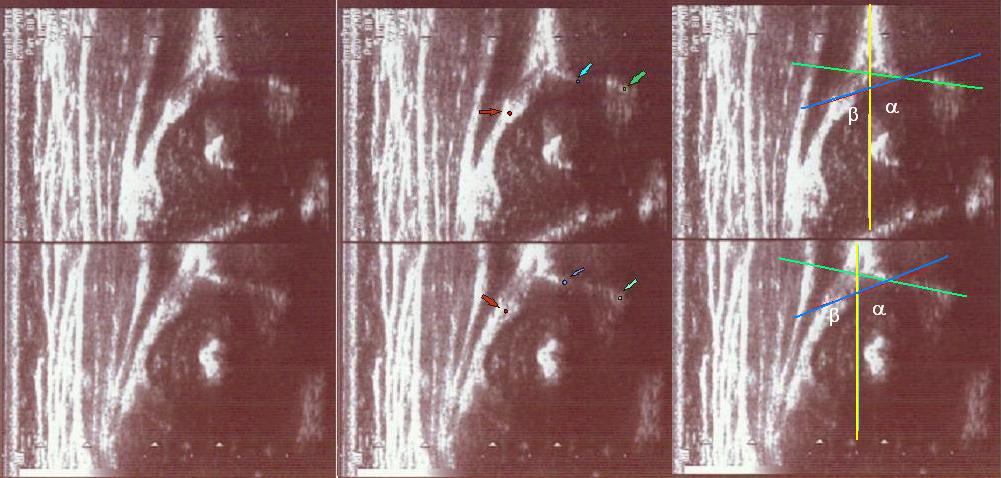

type II/D(up) 4 weeks the bony roof severely deficient ,

the bony rim flattened

the cartilage roof dispalced;

the arrows show labrum (red) ;

the bony rim (yellow);

the lower iliac margin (blue) ,

the bony roof line (green) is extends tangential to the lower iliac margin and tangential to the bony rim

the cartilage roof line(blue) is drown tangential to the bony rim and through the middle point of the labrum

the baseline (yellow) is drown parallel to ilium echo through the point of the junction of the perichondrium,the periosseum and ilium.

type IIc (up) 6 weeks the bony roof severely deficient ,

the cartilage roof still covers ;

the bone roof line (red)

the cartilage roof line(pink)

the baseline (yellow)

type D(up) 1 weeks the bony roof severely deficient ,

the bony roof line (green)

the cartilage roof line(blue)

type I (below) 6 weeks

asymmetry in the loose joint capsule;family DDH ( when it occurs ask always about it)

the bony roof is good

the bony rim blunt

the cartilage roof cover the head;

the bony roof line (blue) is extends tangential to the lower iliac margin and tangent to the bony rim

the cartilage roof line(green) is drown tangential to the bony rim and through the middle point of the labrum echo ;

asymmetry in the loose joint capsule ,family DDH( when it occurs ask always about it)

type Type GN (coming to maturity) (Physiologically immature, border type between I and II) (up ) 6 weeks

the bony roof is adequate